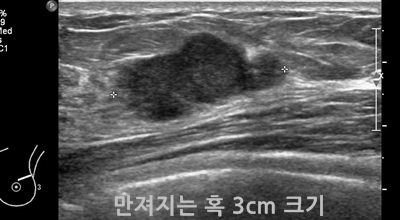

초기에는 통증은 느껴지지 않아요. 하지만 멍울이 만져질 수 있는데 손으로 느낄 만큼 멍울이 만져진다면 유방암 2기, 즉 유방암 초기증상일 확률이 높은데요 멍울이 가슴에 있기도 하지만 겨드랑이에서 만져지기도 해요. 이러한 증상이 나타난다면 바로 병원에 가서 검사를 받아보는 편이 좋아요.

2. 유방암 초기증상 - 유방의 혹

보통 응어리가 잡히는 분들의 40%는 물혹으로 가벼운 질병으로 바로 치유가 되는 경우가 많은데요 20~30%의 확률로 유방암 초기증상일 가능성이 있다고 하죠. 따라서 매일같이 자신의 가슴을 마사지 해주시다 어느 날 응어리가 잡히게 된다면 유방암 검사 초기에 받아 보시기를 권해 드립니다.